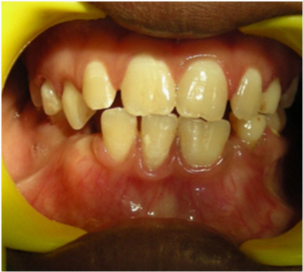

A 10 year old boy reported to the Department of Pedodontics and Preventive Dentistry, Narayana Dental College, Nellore, Andhra Pradesh for routine dental check-up, presented with a large tooth in the lower left front region of the jaw (Figure 1). The boy was not concerned about the aesthetic appearance. The medical and family histories were not significant. Extraoral examination did not show any alterations. Intraoral examination revealed an early mixed dentition period with the presence of one large incisor that was abnormally wide on the left side of the lower arch (Figure 2 and 3). The child had 20 teeth and normal eruption pattern and occlusal status was evident. The double tooth presented a groove upto the cervical third of the crown and hypoplasia on the labial surface (Figure 4). Periapical radiograph displayed the connated incisor with a single root and single pulp canal (Figure 5). The orthopantomograph revealed the presence of double tooth along with the absence of lower left lateral incisor (Figure 6).

Figure 3 Close up view of connated teeth showing a groove that extends upto the cervical third of the crown.